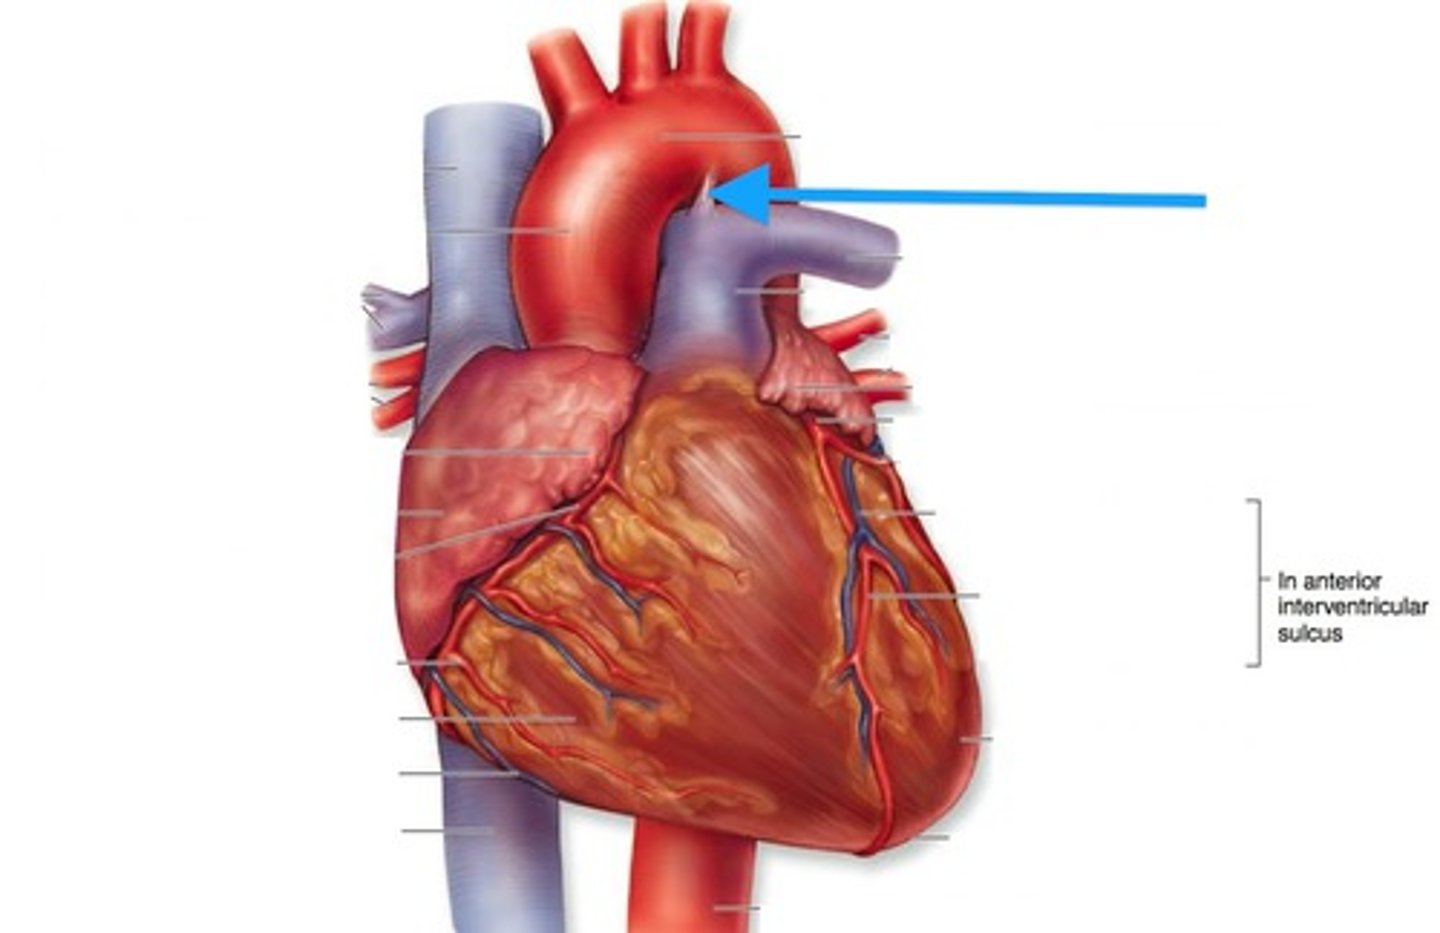

Coronary arteries (right (A) and left(D))

First branch off the base of the aorta

Blocked when aortic semilunar valve opens

Supplies blood to the heart muscles

Marginal artery (C) and Posterior Interventricular artery (B)

Branches of right coronary artery

Anterior Interventricular artery (F) and Circumflex artery (E)

Branches of the left coronary artery